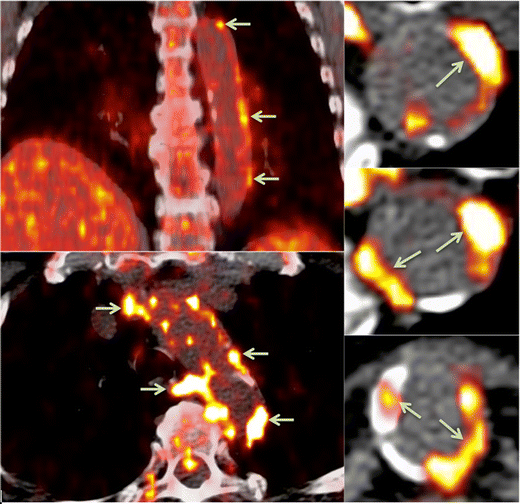

FDG-PET techniques have helped elucidate the systemic nature of atherosclerosis (Fig. 2). FDG uptake correlates closely between neighboring arterial territories, suggesting a global upregulation of inflammation rather than a localized phenomenon [30••]. Joshi et al. demonstrated that FDG uptake in the aorta reflected the clinical severity of coronary syndromes, with a 20 % higher TBR in the aortas of those with a recent myocardial infarction than those with stable angina. Furthermore, within the group with myocardial infarcts, the aortic FDG uptake was higher for those with an ST elevation myocardial infarction than those with a non-ST elevation myocardial infarction [31]. Similarly, carotid SUVmean and TBRmean are significantly higher for cohorts with acute coronary syndrome than for those with chronic stable angina [32].

Fig. 2

FDG-PET/CT showing areas of focal radiotracer uptake in the wall of the descending aorta (arrows)